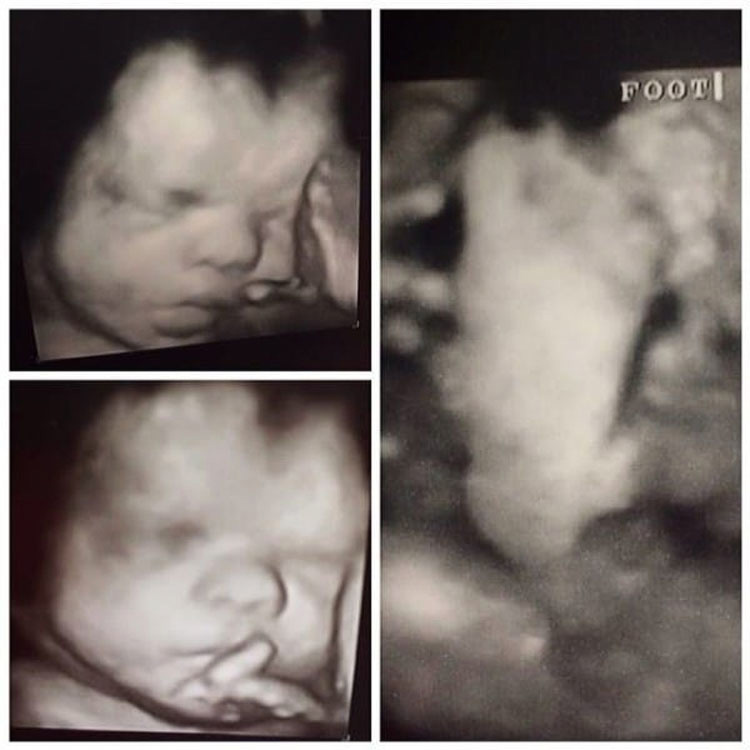

Cuando los médicos vieron que el niño en el interior de la madre, Hannah Peters, no estaba creciendo a la velocidad habitual, se determinó rápidamente que su pequeño bebé probablemente tendría un mal final.

A medida que la fecha de su nacimiento se acercaba más y más, estaban casi totalmente seguros de que el bebé que tenía en su interior no viviría más de dos meses, ya que la vida que se encontraría en el exterior no sería compatible con la del útero.

Le dijeron a Hannah que sólo pesaría 1,300 kg. y que no lloraría cuando naciera porque sería demasiado pequeño y débil. Sin embargo, Hannah mantuvo la esperanza y sentía en su alma que su pequeño bebé iba a ser un luchador. Desde entonces, ha estado actualizando para todo el mundo en un increíble blog cómo lo está haciendo Jude.

Las cosas parecían ir bastante bien hasta que, en la decimotercera semana del embarazo de Hannah, el bebé fue diagnosticado con una rara forma de displasia esquelética.

Muchos especialistas dijeron a la madre que su bebé simplemente no iba a progresar. Que sería muy pequeño y débil y no sería capaz ni de llorar debido al diagnóstico desgarrador. Pero la familia mantuvo su fe, y después de 40 semanas, Hannah logró continuar con su pequeño ángel.